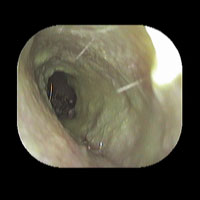

左急性中耳炎(重症)

鼓膜がやや赤くなって腫れています。鼓膜の奥に膿が透けて見えています。抗生剤の内服で鼓膜切開を行わずに22日目で治りました。

初診日